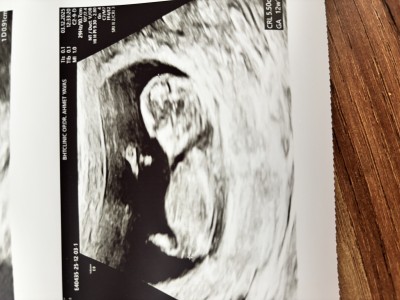

Yorumlarınızı bekliyorum kızlar. Ok ile gösterilen yer cinsiyet doktorum yeni yıldan önce geldiğinizde müjdeyi veririm dedi bir şey söylemedi

Gebelik haftası 12+

Nub teorisine göre kız bebeginiz

Kiza benziyo cizgiisi var